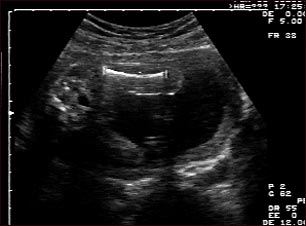

Ultrasonido de un feto normal; medidas del fémur

Ultrasonido normal a las 19 semanas de gestación en el cual se puede apreciar una imagen clara del fémur (hueso grande de la pierna) izquierdo, en el centro y hacia la parte superior de la pantalla.